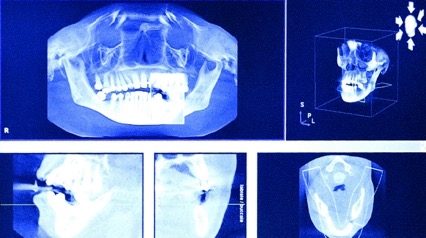

Con un apposito software è possibile pianificare e programmare con massima precisione e scrupolosità l’intervento d’implantologia dentale definendo la dimensione esatta degli impianti rispetto al dente da sostituire e alla conformazione anatomica del paziente. I dati ottenuti da una TAC 3D (un’apparecchiatura radiologica di ultima generazione, in grado di ottenere immagini tridimensionali estremamente dettagliate in pochi secondi, impossibili con qualsiasi altro esame radiografico) vengono trasformati in una mascherina appositamente pre-forata che permette di operare come programmato dal computer. L’intervento diventa meno invasivo poichè l’inserimento degli impianti non necessita di tagli e punti, perciò con trauma minimo, senza gonfiore e dolore. Si possono inserire anche molti impianti in un’unica seduta.